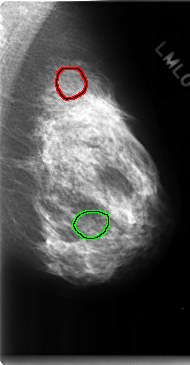

C_0150_1.LEFT_MLO

LEFT_MLO LINES 4736 PIXELS_PER_LINE 2464 BITS_PER_PIXEL 12 RESOLUTION 50 OVERLAY

FILE: C_0150_1.LEFT_MLO.OVERLAY

TOTAL_ABNORMALITIES 2

ABNORMALITY 1

LESION_TYPE CALCIFICATION TYPE AMORPHOUS DISTRIBUTION CLUSTERED

ASSESSMENT 4

SUBTLETY 1

PATHOLOGY BENIGN

TOTAL_OUTLINES 1

ABNORMALITY 2

PATHOLOGY MALIGNANT